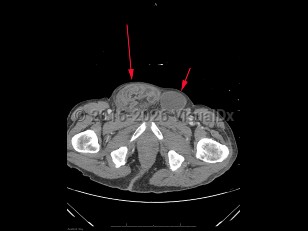

Inguinal hernia in Child

An inguinal hernia is a protrusion of an intraabdominal organ, often the small bowel, through an opening in the inguinal area of the abdominal wall. Inguinal hernias are very common, occurring in approximately 5% of the general population. Risk factors include a personal / family history of hernias, history of prior hernia or hernia repair, advanced age, male sex, smoking, prior abdominal wall injury, chronic constipation, and chronic cough. Inguinal hernias can be congenital or acquired. They are caused by a weakening or failed closure of fibromuscular groin tissue.

Inguinal hernias can be classified as either direct or indirect, determined by their location. An indirect inguinal hernia's defect is at the internal inguinal ring. A direct inguinal hernia's defect is medial to the inferior epigastric vessels within Hesselbach's triangle. Indirect inguinal hernias are more common and are often attributed to congenital defects; direct inguinal hernias are often acquired in the setting of connective tissue weaknesses.